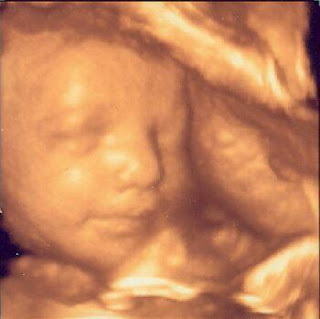

And the time is almost here 2 days till our 3D ultrasound!!!! Above is an example of what a 3D/4D ultrasound looks like. This baby is at 27 weeks which is what the twins will be Saturday. I can't wait to see their little features. I was really hoping we would be able to get a 3D picture of both of their faces in the same shot, but unfortunately since one is breach and one is head down we wont be able to. Hopefully they will cooperate and we will get some great face shots. My next blog will be a recap of our 3D ultrasound, so stay tuned. Goodnight all!!!